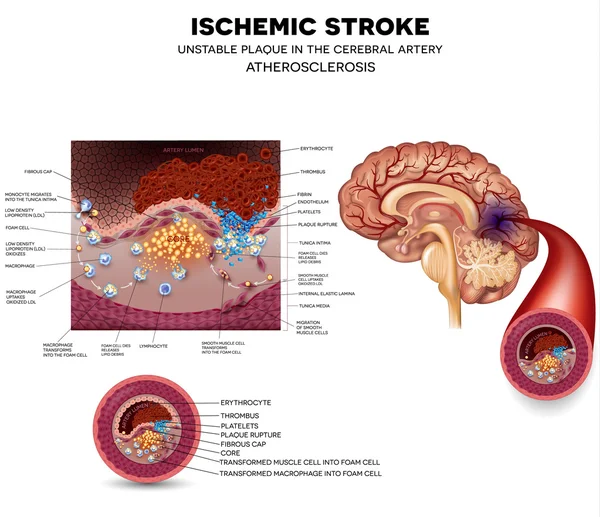

Pin on Neuro

(PDF) Vessel wall differences between middle cerebral artery and …

Frontiers | Factors for Enhancement of Intracranial Atherosclerosis in …